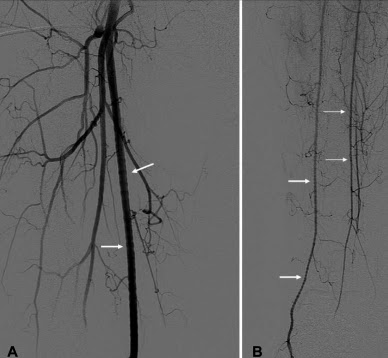

So instead, you have to go antegrade... but how do you find the upstream entrance to the thoracic duct? The trick is to perform a pedal lymphangiogram first as a road map. First lymphazurin is injected into the subcutaneous soft tissues (at the interdigital spaces of the first, second, and third toes). A small incision is then made and the colored lymphazurin ("lymph" + "azure") highlights the foot lymphatic channels in the subcutaneous tissues. A lymphatic channel is then selected and cannulated with a 30 gauge catheter, after which lipiodol is slowly infused (below). Multiple lymphatic channels can be cannulated to try to increase the amount of contrast in the lymphatic system.

| Lipiodol contrast extending up the lymphatics of the lower extremity toward the pelvis, and from there to the abdomen and cisterna chyli. |